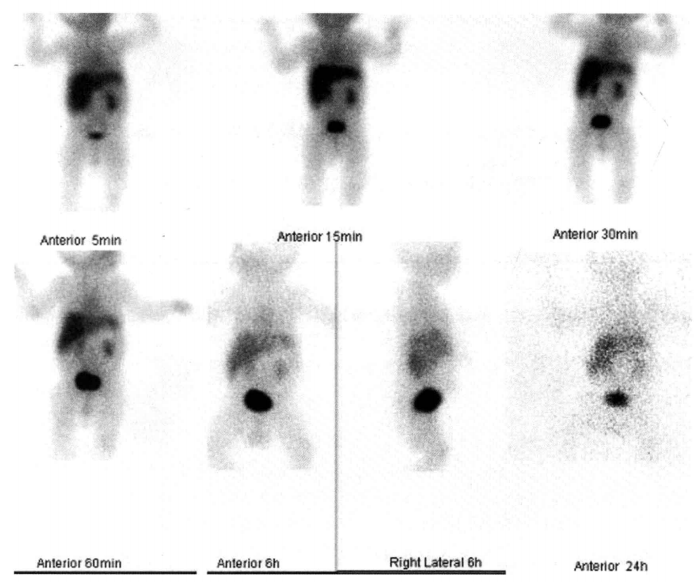

内分泌系统:

甲状腺情况怎么样?

目前甲状腺疾病如甲亢、甲状腺结节、甲状腺癌好发,甲状腺显像不仅用于甲状腺功能性评估如评估甲亢病情、甲状腺炎辅助诊断,还能用于协助诊断甲状腺结节性质、评估甲状腺癌术后情况、判断颈胸部肿块与甲状腺关节以及寻找异位甲状腺等。此外还有甲状旁腺显像可诊断甲状旁腺功能亢进、肾上腺显像用于诊断嗜铬细胞瘤等。

案例:胸骨后占位患者,甲状腺显像检查结果提示为胸骨后甲状腺肿。